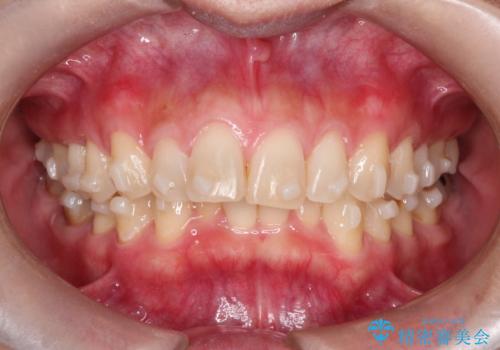

- 前歯の凸凹を主訴に来院されました。

臼歯部の遠心移動を行いながらスペースを作り、インビザラインにて前歯をきれいに並べることができました。

今回の治療計画では臼歯部の遠心移動とIPRを行っています。